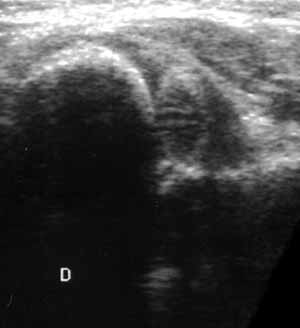

Рис. 8. Ультразвуковое изображение (Слева) и схема (Справа) вывиха сустава. Головка бедренной кости располагается вне полости сустава, децентрация ее происходит чаще латерально. Отмечается симптом “пустой“ ацетабулярной впадины. При подвывихе и вывихе бедра угол альфа < 43о, а угол бетта > 77о.